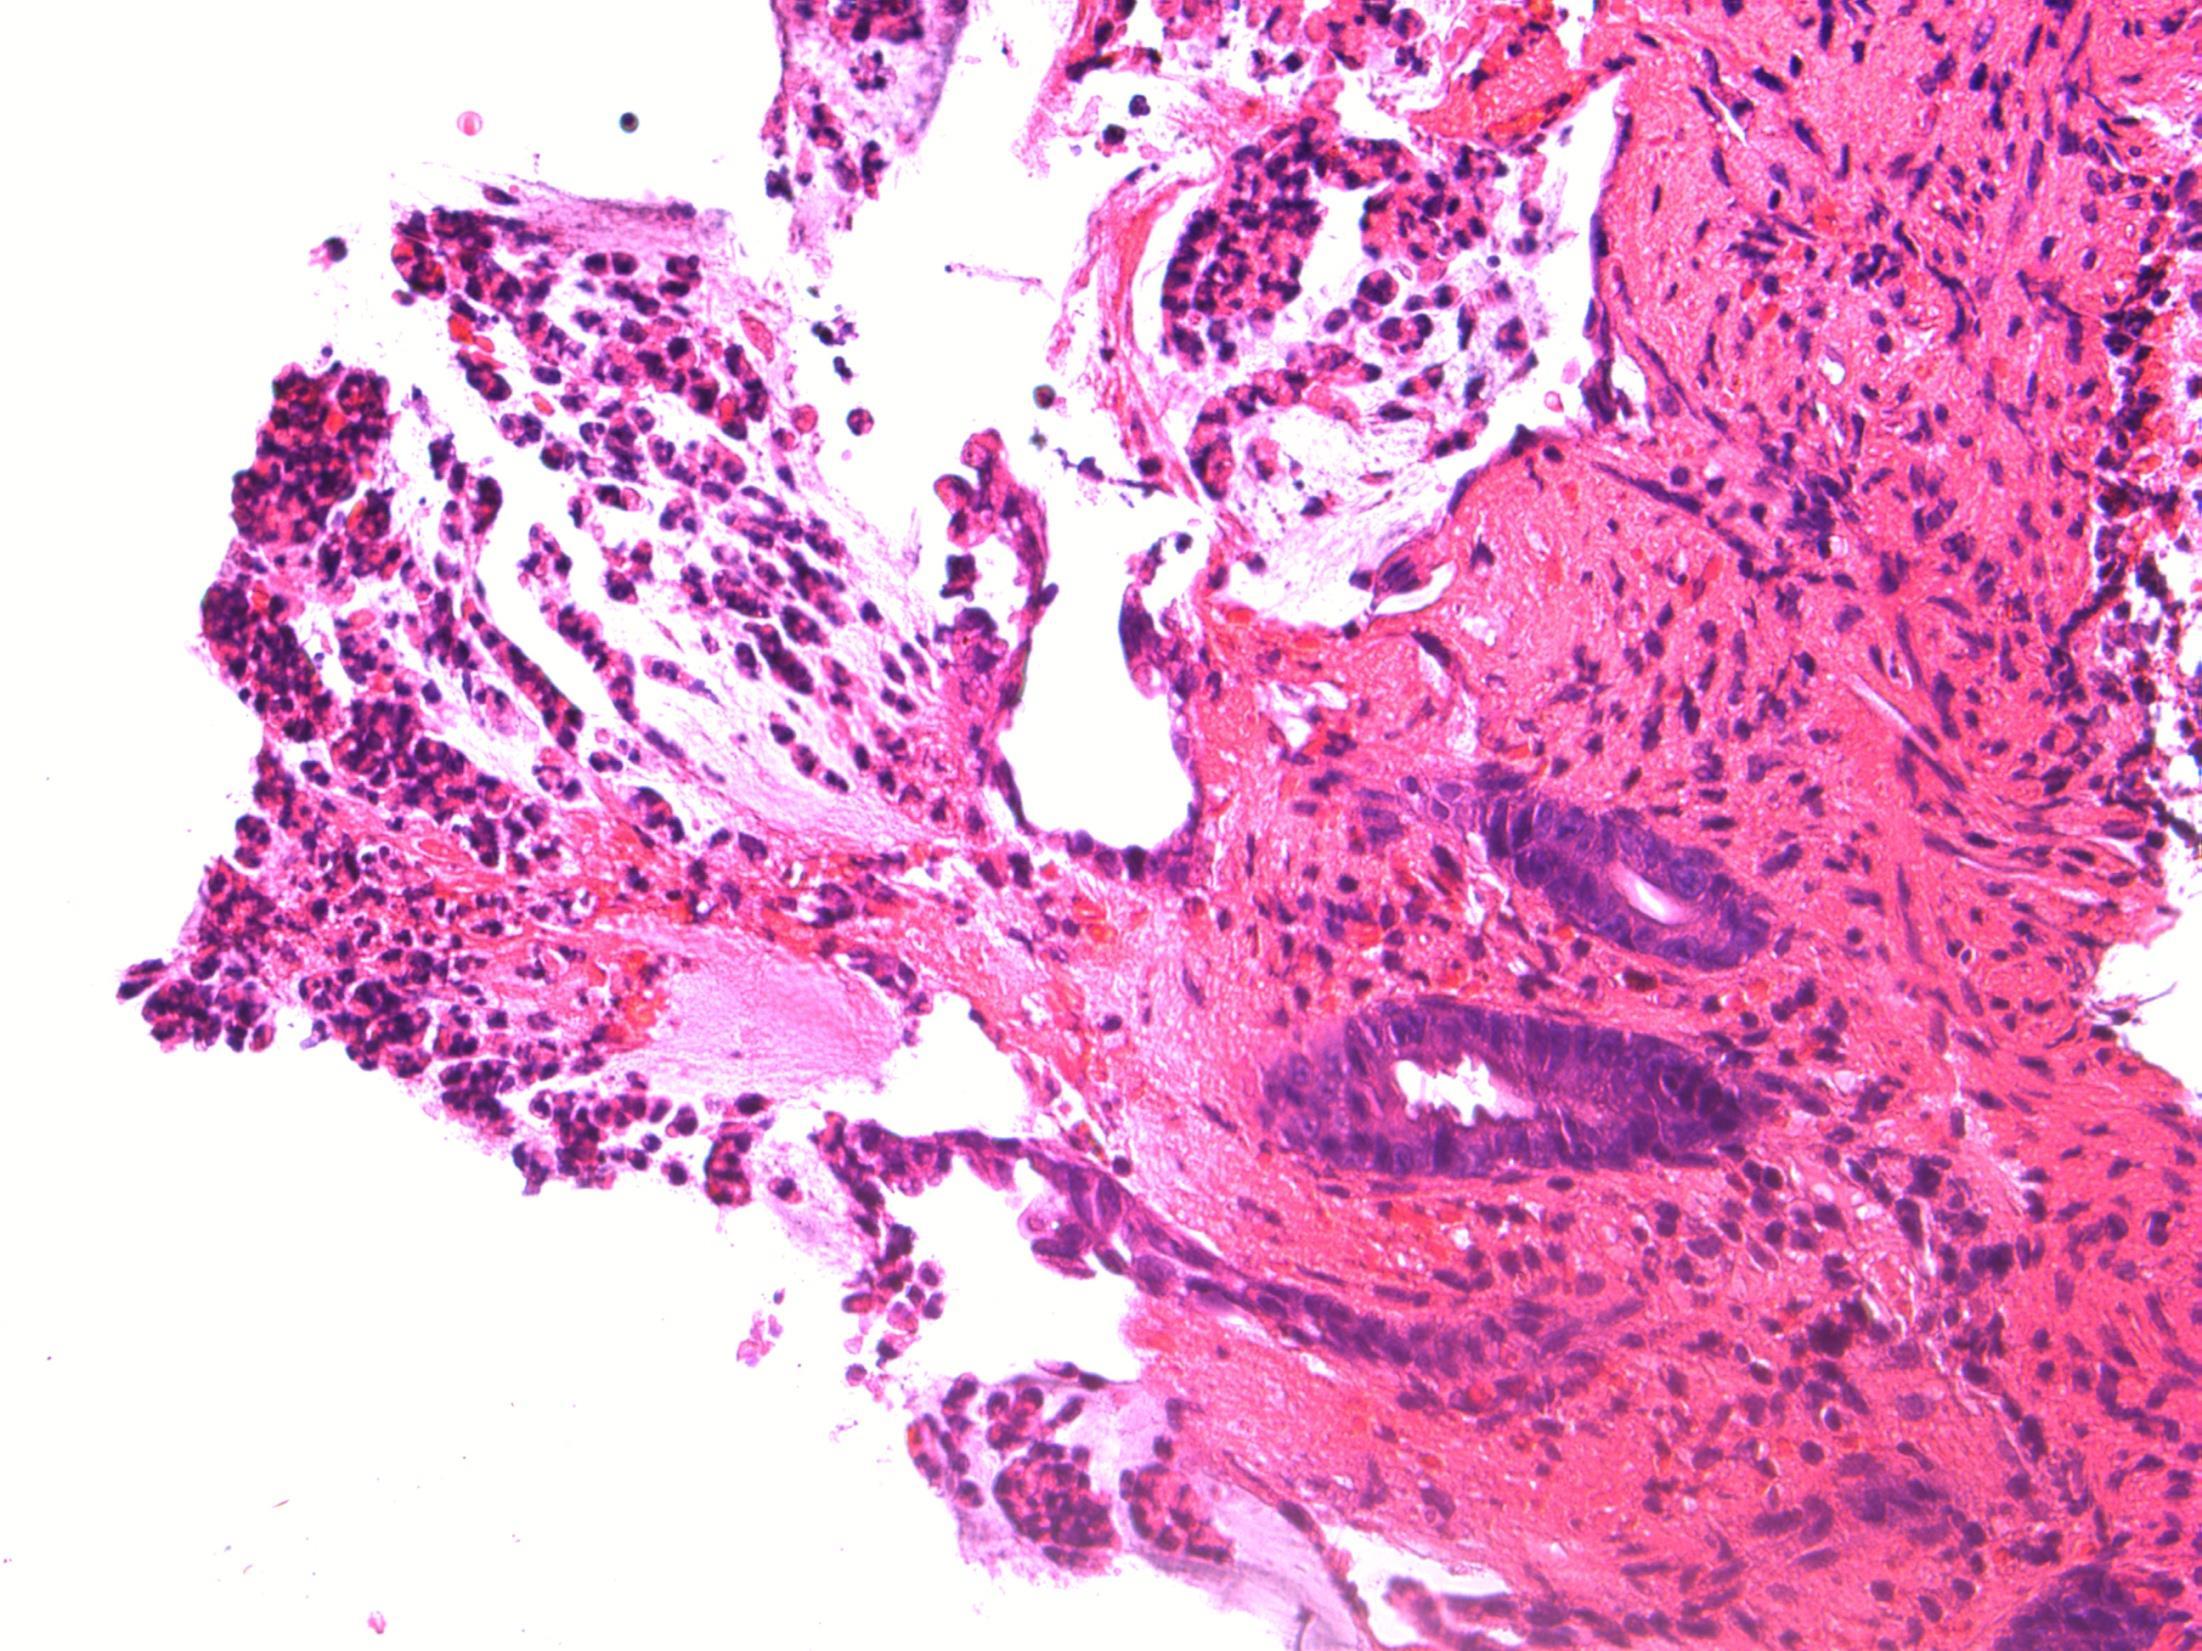

Pseudomembranous colitis

• Description: Patchy necrosis of mucosa, with mushroom shaped fibrinopurulent exudates on surface, crypt withering, hyalinisation of lamina propria

• Diagnosis: Pseudomembranous colitis

Differential diagnosis: Acute ischaemic colitis (can be very difficult – a lot depends on the history and clinical context, but usually more localised / segmental and full thickness necrosis)

• Plan: Correlate with microbiology, antibiotic history, endoscopy etc

• Comments: PMC typically follows antibiotic administration, which correlates well with the history provided. Caused due to toxins of C. difficile